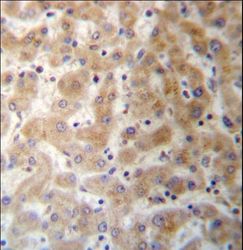

- Experimental details

- DHFRL1 Antibody immunohistochemistry of formalin-fixed and paraffin-embedded human liver tissue followed by peroxidase-conjugated secondary antibody and DAB staining.